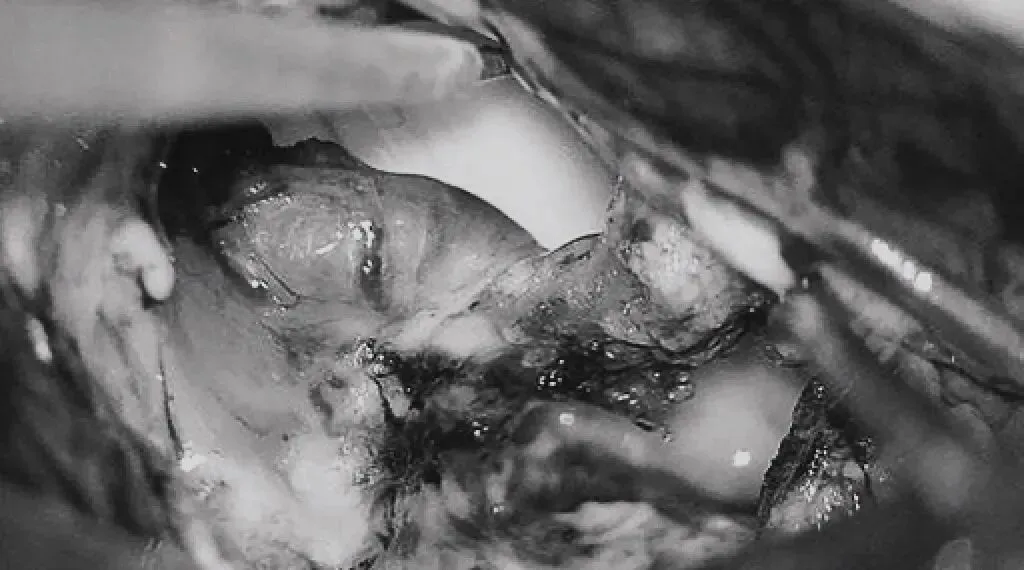

在透明隔底部保留FoM、穹窿和右侧SepV。

引流静脉变黑。